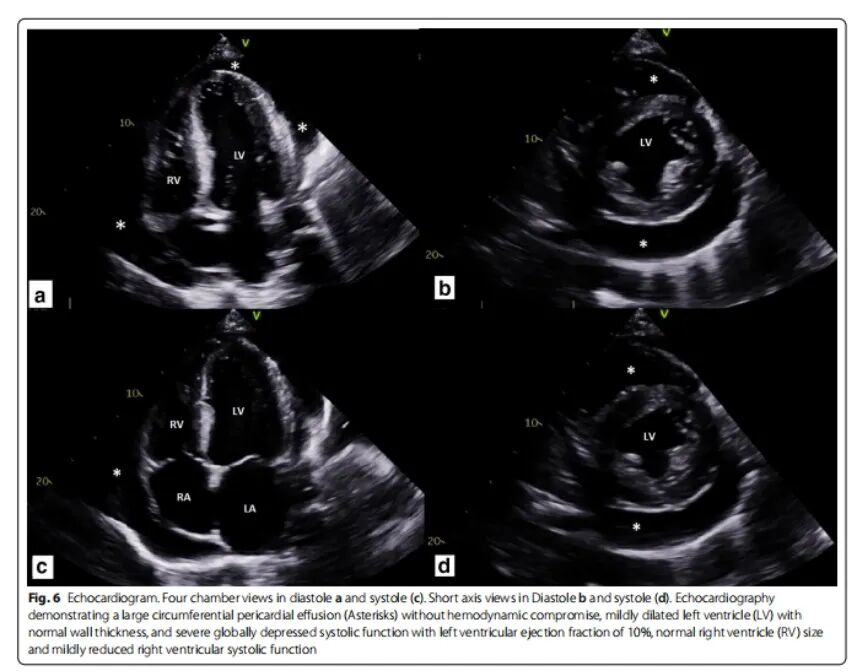

23岁青年男性,呼吸困难、胸痛伴咯血2周。既往G6PD缺乏病史及肥胖。吸食大麻。查体:BP 220/110 mmHg,心率120次/min,双肺听诊哮鸣音。实验室检查:肌酐升高2.03 mg/dl(179 μmol/l),微量蛋白尿。CRP 80 mg/L,ESR 67 mm/h。AN A 1:160阳性,RF、ANCA、补体、抗Sm抗体、抗组胺抗体均阴性。心脏彩超:EF 40%,左室肥厚,少量心包积液。胸部CT提示双侧小叶中心渗出,纵隔淋巴结肿大,心包积液。肾脏彩超及肾动脉彩超均无异常。外科胸腔镜右肺活检切除术,病理提示显微镜下多血管炎。泼尼松60 mg/d口服,症状无缓解,复查肺部CT示渗出加重。[Mollaeian A, et al. Auto Immun Highlights, 2021, 12(1):1.]

图片